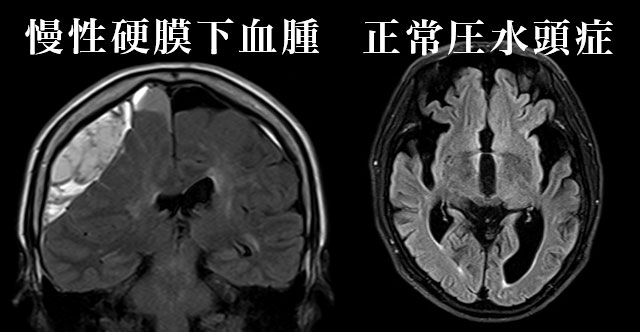

認知症の原因はアルツハイマー病だけではありません。

脳出血・脳梗塞に加え、「治療可能な認知症」である正常圧水頭症や慢性硬膜下血腫などがあります。

本コースでは、これらを診断可能な脳MRIに、アルツハイマー病の評価に用いられるVSRAD(統計解析)を加え総合的に診断します。

もの忘れや将来の認知症が心配な方への専門プランです。